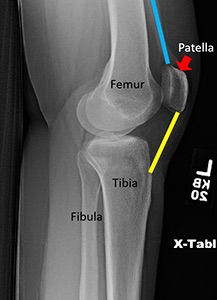

Understanding Knee Fractures

A knee fracture refers to a break in any of the bones forming the knee joint—typically the distal femur (thigh bone), proximal tibia (shin bone), or patella (kneecap).